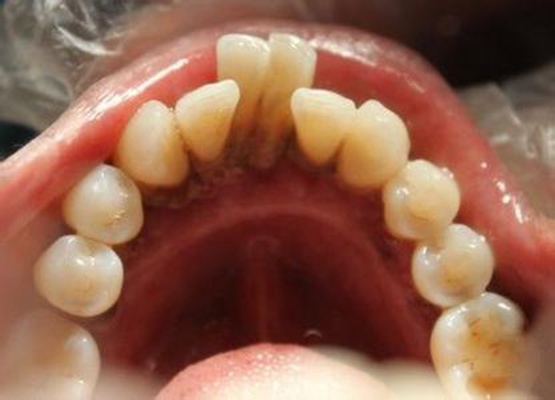

牙周袋 (47)